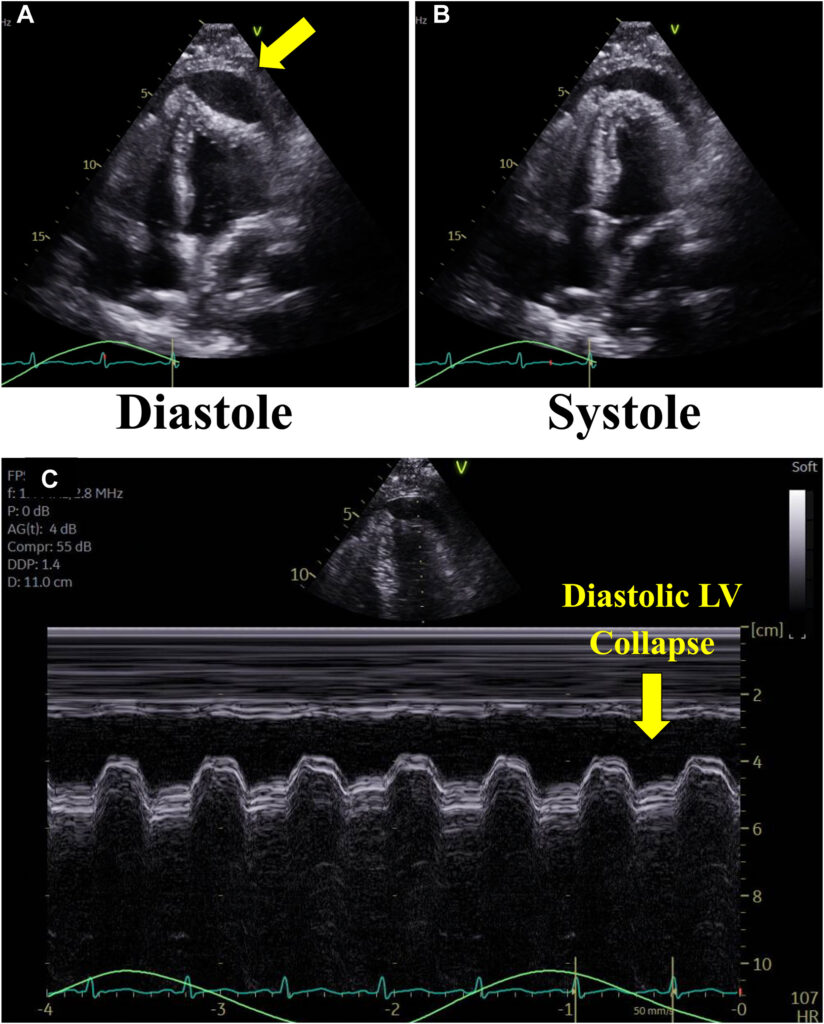

Havia colapso diastólico da região apical e da parede lateral do ventrículo esquerdo, além do colapso do VD.

Também foi observado um espessamento do pericárdio (4 mm) com tethering da parede livre do VD e da parede lateral do VE caracterizado pela ausência da movimentação tipo deslizamento entre os folhetos parietal e visceral do pericárdio.